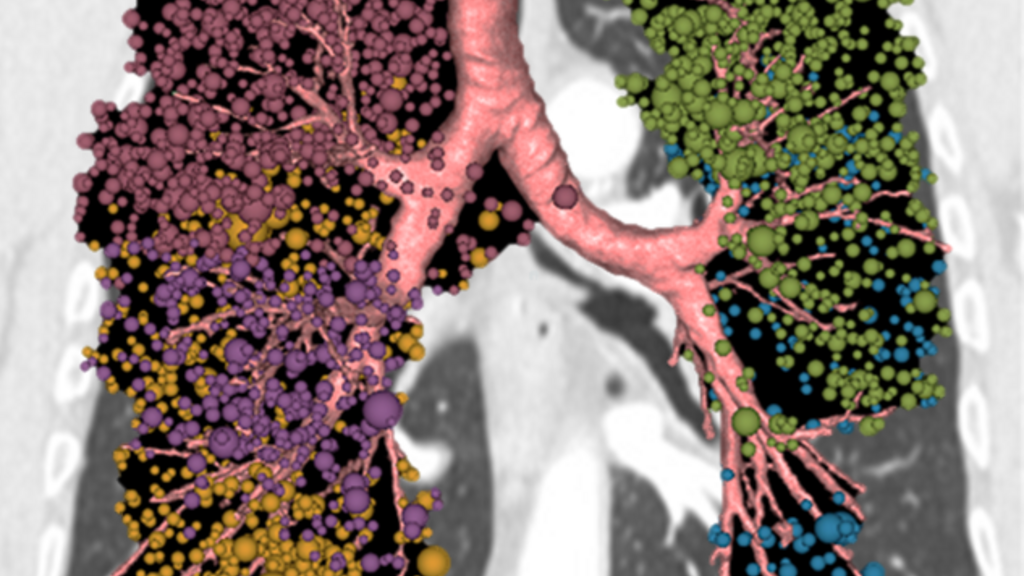

lung cancer risk image

Radiomics for COPD and Association with Lung Cancer Risk

We are interested in the utilization of CT imaging to explore lung disease etiology and subtypes.